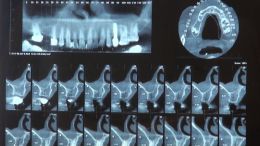

اصول مبانی GBR

+ اساتید گروه علمی بن تاژ پارس (زیرنظر پروفسور غلامی)

- جراحي توسط دکتر عميد از اساتید گروه علمی بن تاژ